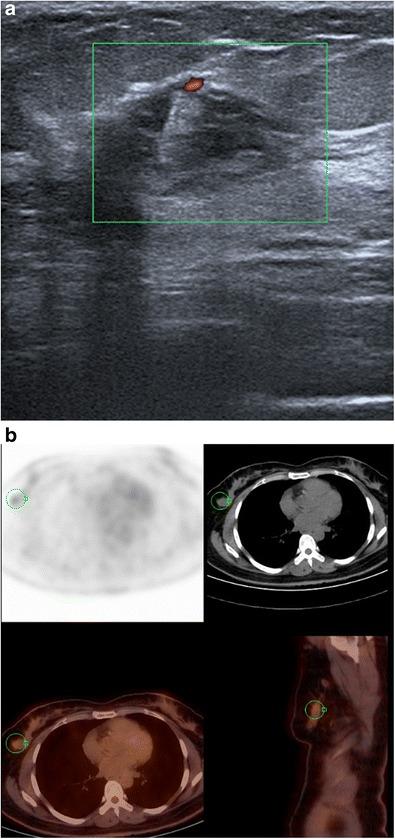

Hyperechogenicity is a sign classically reported to be in favour of a benign lesion and can be observed in many types of benign breast lesions such as hamartoma, lipoma, angiolipoma, haemangioma, haematoma, fat necrosis, fibrosis and galactocele, among others. However, some rare malignant breast lesions can also present a hyperechoic appearance. Most of these hyperechoic malignant lesions present other characteristics that are more typically suggestive of malignancy such as posterior shadowing, a more vertical axis or irregular margins that help to guide the diagnosis. Post magnetic resonance imaging, second-look ultrasound may visualise hyperechoic malignant lesions that would not have been identified at first sight and radiologists must know how to recognise these lesions.

• Some rare malignant breast lesions can present a hyperechoic appearance. • Malignant lesions present other characteristics that are suggestive of malignancy. • An echogenic mass with fat density on mammography does not require biopsy.

高回声是一种传统上被认为提示良性病变的征象,可在多种类型的乳腺良性病变中观察到,如错构瘤、脂肪瘤、血管脂肪瘤、血管瘤、血肿、脂肪坏死、纤维化和积乳囊肿等。然而,一些罕见的乳腺恶性病变也可呈现高回声表现。这些高回声恶性病变大多还具有其他更典型的提示恶性的特征,如后方声影、更垂直的长轴或不规则边缘,有助于指导诊断。磁共振成像后,二次超声检查可能会发现初次检查未发现的高回声恶性病变,放射科医生必须知道如何识别这些病变。

• 一些罕见的乳腺恶性病变可呈现高回声表现。• 恶性病变具有其他提示恶性的特征。• 乳腺钼靶显示脂肪密度的高回声肿块无需活检。